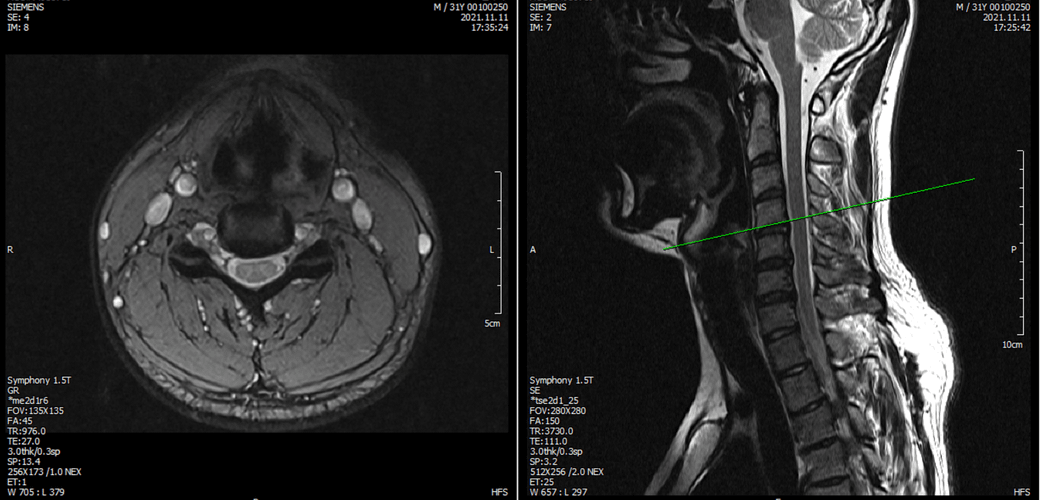

아래는 저의 경추과 요추 MRI 사진 첨부합니다.

※우리들병원 (신경외과 대표원장) : 경추,요추 MRI 촬영했고 요추는 매우 건강하고 경추에는 일자목에 퇴행성 디스크가 보이지만 한쪽팔에 저림이나 힘빠짐을 유발할 정도는 절대아니고, 다른 원인을 찾아야한다고 했습니다.

※동네 신경외과 : 앞서 모든 설명은 잘못된것, 디스크가 나이에 비해 매우 심하고 일자목이 아닌 역C자목임, 경추에 디스크가 찢어진 것이 보이는데 이런 구조적 변화가 화학적반응을 일으켜 신경을 자극할 수 있음. 약을 먹어야하고 안되면 주사치료해야함, 300만원짜리 교정치료도 해야함.

3명이 디스크가 아니라고 하는데 1명이 디스크일수 있다고 하니까 조금 어렵습니다. 경추디스크가 약간은 있으니 팔저림은 설명할수 있다해도 다리저림은 설명이 안됩니다.. MRI 결과상 요추는 매우 건강하다고 하셨거든요.